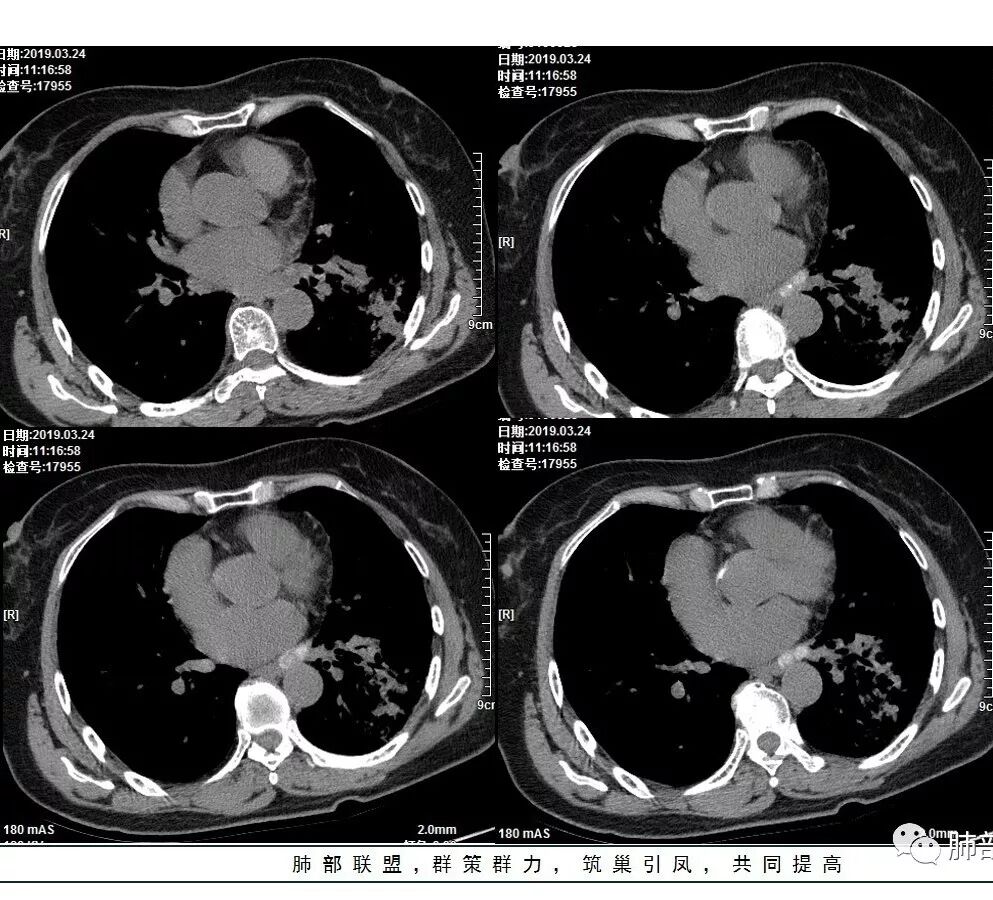

女性,57岁或67岁,咳嗽气短2月,伴发热2天。肿标及血常规(一)。左下肺实变+GGO,实变区增强强化,镜下见左下支气管狭窄,最后一次CT(4.11)较第一次CT(3.24)病灶有吸收。个别图像看不清(Tspot)。考虑:一元:肺炎型肺癌丶肺结核丶普通炎症?二元:结核合并癌?

2.左肺下叶片状影及多数有边界的结节影,较散,多形性,密度不均(注意许多老师提到这个特点还是比较明显的)。左肺下叶体积未见缩小。

3.病灶强化比较明显。

4.左下叶支气管壁增厚,管腔不均匀狭窄,没有堵塞

5.肺门纵隔见增大钙化淋巴结。提示曾经存在慢性病损可能。

1.前述特点除强化外都还是很容易让人首先想到肺结核的可能性。结核是常见病。注意肉芽肿明显的结核灶可以观察到强化。

2.淀粉样变性病变支气管改变一般会更广泛,较少出现单叶肺的如此大片影。

3.腺癌不大会出现较散的腺泡样结节影,更不会出现如本例的支气管改变。增大钙化的淋巴结也很难相互关联。

4.相关支气管未见腔内结节及阻塞,女性患者,鳞癌的可能性更小。